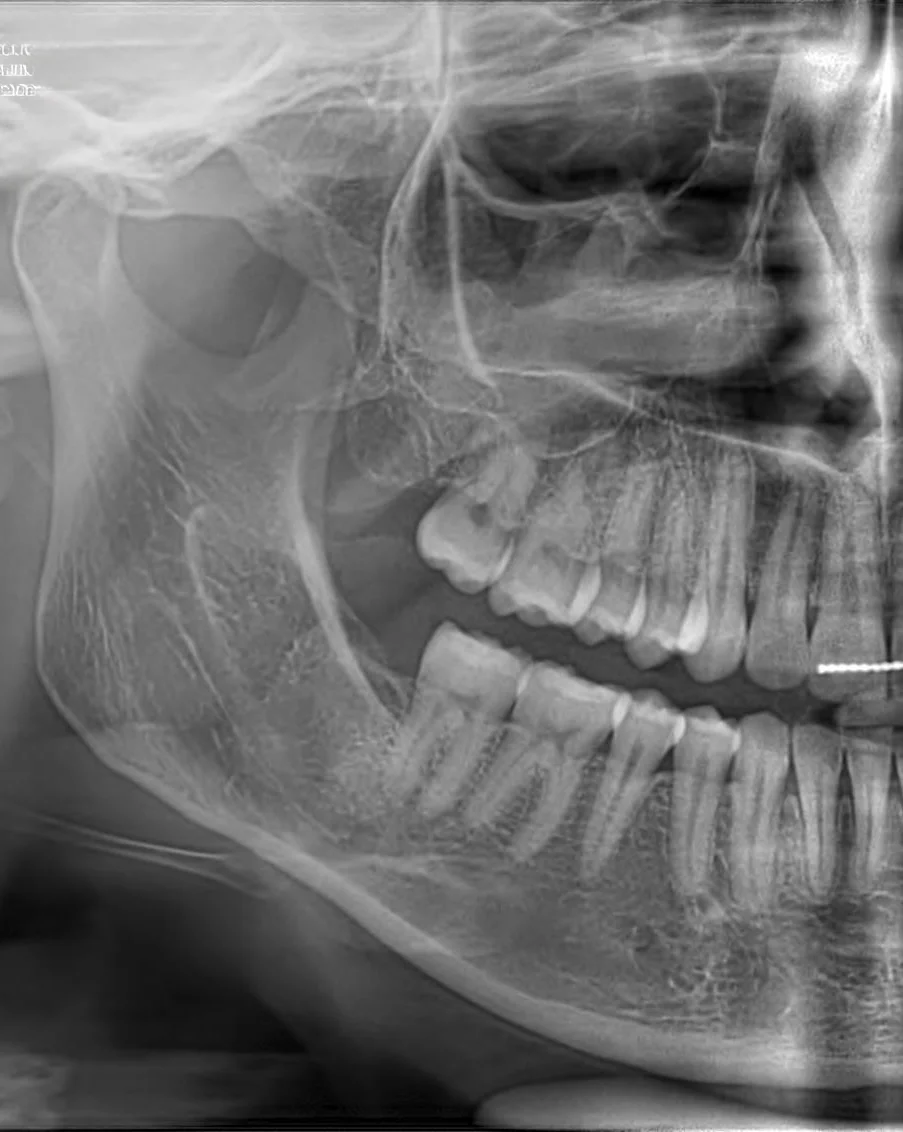

Przed

Profesjonalna chirurgia stomatologiczna z widocznym efektem leczenia

Każdy zabieg poprzedzony jest dokładną diagnostyką, najczęściej w oparciu o zdjęcie RTG pantomograficzne lub CBCT 3D. Dbamy o bezbolesny przebieg, komfort pacjenta oraz szybkie gojenie poprzez stosowanie nowoczesnych technik chirurgicznych.